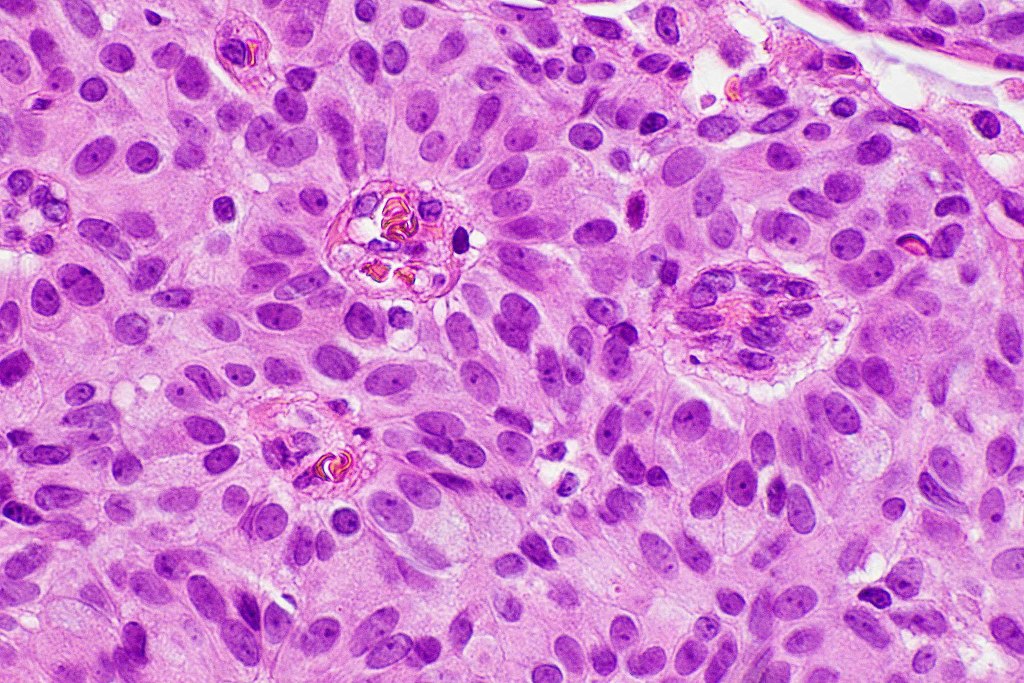

•EMPSGCa– multiple nodules of uniform epithelial cells with vesicular nuclei & small nucleoli

•+/- intracytoplasmic mucin

•No significant pleomorphism

•Few mitoses

•No abnormal mitoses